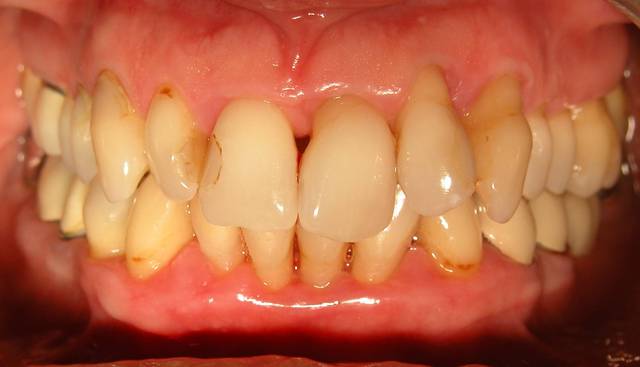

Voici le cas d'une patiente que j'ai traité pour une parodontite chronique.

Donc il s'agite d'une patient adressée par un confrère pour un avis paro avant un traitement ODf. La patiente a cinquante cinq ans. Elle fume des cigares, des problèmes d'hygiène. Je dignostique une parodntite chronique que j'ai traité en non chirurgical. La patiente est en observation avant d'entamer un traitement prothétique plutôt qu'ODF.

La consultation: DSCN 7002

1 mois après la consultation et motivation à l'hygiène: DSCN 7502

Le jour de la lithotriptie: DSCN 7030

6 mois après: DSCN 0013

Le traitement ODF vu les pertes d'ancrage nécessitait une contention. La patiente était pressée, avec la prothèse on réalisait la contention et on pourra jouer sur l'esthétique. Bon là c'est son praticien, qui voit avec sa patiente. Pour moi ce qui est important c'est la contention, car il y a peu d'ancrage et gros troubles occlusaux.